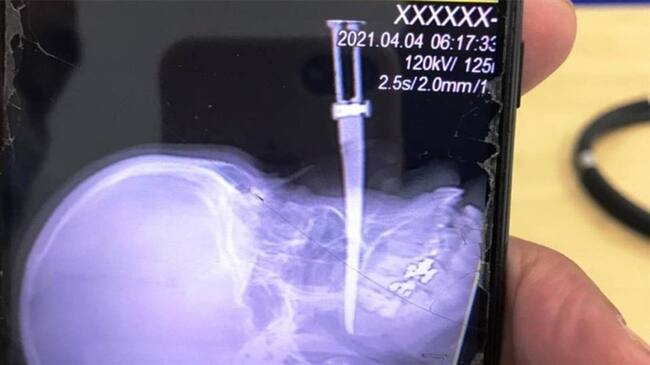

Hombre acuchilló a mujer en Cartagena. Foto: Cortesía Antonio Canchila(Thot)

En medio del rechazo que ha causado en ataque del cual fue víctima Yoledis Montalbán Hernández, la mujer a la que un hombre hirió con un cuchillo que le quedó incrustada en la cara, en medio de un atraco en el barrio El Pozón, sur de Cartagena, la Policía Metropolitana anunció que adelantan las labores para dar con el paradero del agresor y capturarlo.

De Montalbán se conoció que fue intervenida quirúrgicamente en la Clínica La Ermita, donde se recupera satisfactoriamente, con el acompañamiento de su familia.